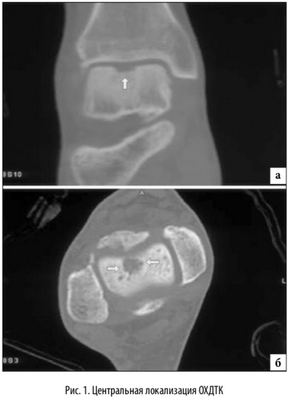

Наиболее распространенной локализацией остеохондральных повреждений таранной кости является переднелатеральной и заднемедиальной край суставной поверхности таранной кости. Исследование, основанное на изучении МРТ данных, проведенное Hembree с соавт. [14], определило, что большинство выявляемых локализаций остеохондральных повреждений таранной кости располагались медиально и центрально [15]. Независимо от этого, латеральная локализация данных повреждений связана с травмой от 93% до 98% случаев. Однако, было отмечено, что повреждения латеральной локализации в основном имеют меньшую и правильную овальную форму и возникают при эверсионных движениях в максимальном подошвенном сгибании стопы [16]. Медиальные повреждения связаны с острой травмой реже, от 61% до 70% [5]. Считается, что медиальные поврежде ния, вызваны повторяющейся микротравмой, вызванной соударением медиального края суставной поверхности таранной кости о суставную поверхность большеберцовой кости в момент максимальной супинации стопы. Медиально локализующиеся повреждения глубже, кратерообразной формы, и образуются при максимальном подошвенном сгибании стопы [16]. Остеохондральные повреждения с центральной локализацией имеют мультифакторный механизм образования и наиболее сложны в плане хирургического лечения (рис. 1).

МРТ является ценным инструментом в комплексе диагностики ОХПТК для оценки отека костной ткани, а также выявления скрытых повреждений субхондральной кости и хрящевого покрытия, которые могут быть пропущены при стандартных рентгенограммах или даже КТ. МРТ - самый лучший инструмент оценки для определения стабильности и жизнеспособности фрагмента таранной кости при его отслоении и эта информация может быть решающей в тактике выбора того или иного метода хирургического лечения. Однако, для определения размеров отслоившегося фрагмента таранной кости наилучший метод КТ, так как данные размеров по МРТ могут не соответствовать действительности в сторону переоценки последних. Hepple с соавторами изучив многочисленные данные МРТ диагностики разработали систему классификации ОХПТК на основе этого метода (Табл. 2) [23]. Однако, наиболее широко принятая система классификации, основанная на КТ-это классификация Ferkel и Sgalione (Табл. 3; Рисунок 4) [24]. Классифицировать ОХПТК также возможно выполнить интраоперационно, на основе артроскопических данных о состоянии остеохондрального поражения. Наиболее широко используется система Ferkel/Cheng (Табл. 4) [25], эта система классификации, в отличие от обычных рентгенограмм, КТ и МРТ, лучше всего взаимосвязана с исходами лечения пациентов.